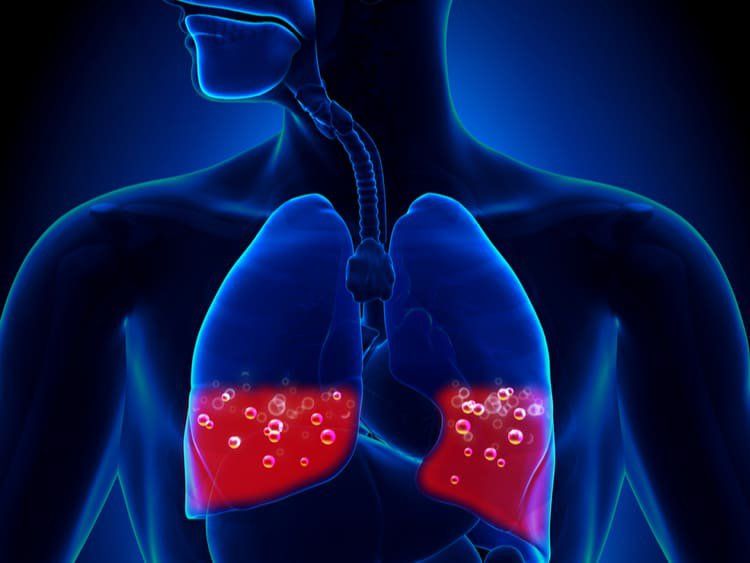

Chọc hút dịch màng phổi nhằm mục đích hút dịch, máu, mủ, khí có nhiều trong khoang màng phổi gây suy hô hấp cấp nhằm hạn chế nguyên nhân gây tử vong.

- Tràn khí màng phổi trên một tổn thương phổi: giãn phế nang, xơ phổi, lao phổi, tụ cầu phổi,...

- Tràn máu màng phổi.

- Tràn mủ màng phổi.

- Tràn dịch hoặc tràn máu màng phổi tái phát nhanh (nhằm gây dính).